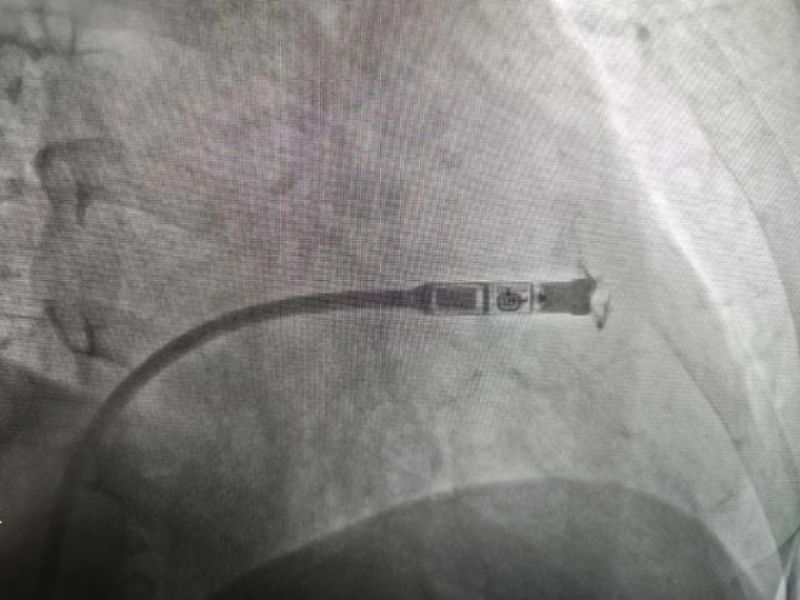

手術過程:經過充分的術前討論,在延安大學咸陽醫院心血管病院吳棟梁院長、劉雄濤副院長的指導與支持下,李陽教授、何克強主治醫師、辛浩主治醫師與導管室介入團隊的共同努力下,經過超聲科、心電中心等多學科協作,成功為患者植入雙腔無導線永久起搏器,術后第二天患者在起搏器保障下經藥物治療恢復正常的竇性心律。目前患者心臟情況及腦梗均恢復良好,已順利出院。

科普:Micra無導線起搏器號稱“世界最小起搏器”,無需植入心內膜導線,也無需在胸前皮下制作囊袋放置脈沖發生器(起搏器),手術僅需局部麻醉,通過股靜脈穿刺,將起搏器經導管植入心腔內,手術時間短,減少出血、血腫及感染風險,術后恢復快,肢體活動不受限,無異物感。

優勢:比傳統起搏器體積減少93%,體積更小,重量僅2g,類似一顆維生素膠囊;雖體積只有傳統起搏器十分之一,但其小小身體儲存大能量,續航時間超過12年,整個手術過程平均約30分鐘,植入成功率高,術后8-12小時即可下床活動,術后1-2天即可出院;兼容1.5T(特斯拉)/3.0T全身核磁共振掃描。滿足患者植入Micra之后疾病的診斷和治療需求。